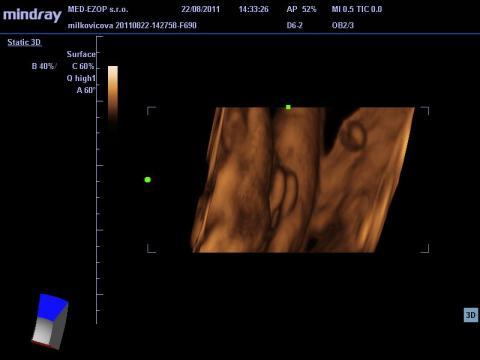

Chlapec, alebo dievča?

Dobrý deň, poprosím o váš názor, nakoľko som dosť napätá, vzhľadom na tlak okolia, manžela, ktorý túži po vyhranenom pohlaví. Raz mi hovoria na UZ, že to bude chlapec, raz dievča. Naposledy som bola v 34tt. Prikladám foto. Aký je váš názor? Dá sa to jednoznačne potvrdiť? Ďakujem

Pokiaľ ani lekári nie sú si na 100% istí, tak s tým nič nenarobíte a dozviete sa to až po pôrode. Ja si osobne myslím, podľa fotky, ktorú ste poskytla, že to vypadá skôr na dievčatko.

No dle mého názoru to vypadá na chlapečka, 2 varlátka a směrem dolu pinďourek. No nevím ale přeju vám to.

Ale toto je myslím foto odzadu, kolienka hore...prečo je tam tá ryha medzi?

ja som to videla rovnako ako máte Vy na foto, podľa mňa je to dievčatko, aj moja dcéra to tak mala.